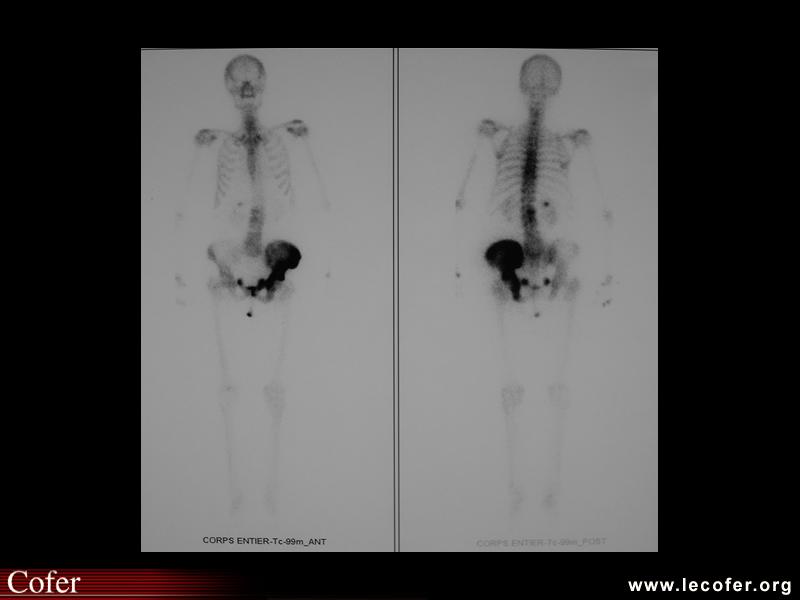

Ostéonécrose aseptique des deux têtes fémorales